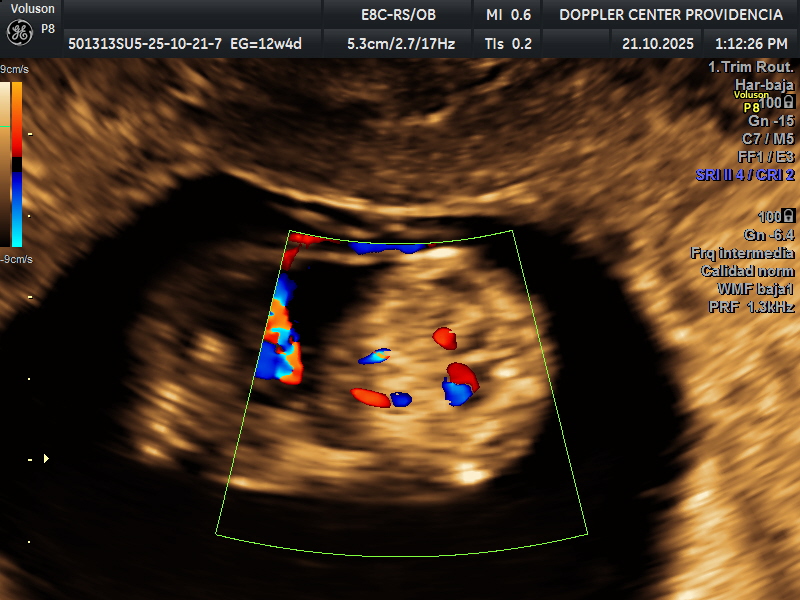

Es una técnica especializada de ultrasonido que utiliza el efecto Doppler para evaluar el flujo sanguíneo en el sistema circulatorio del feto y la madre durante el embarazo.

Se usa principalmente para evaluar el flujo sanguíneo en la placenta, el cordón umbilical y los vasos sanguíneos de la madre y el feto. Esto proporciona información valiosa sobre la salud del embarazo y la circulación fetal.

• Eco Doppler 11-14 semanas